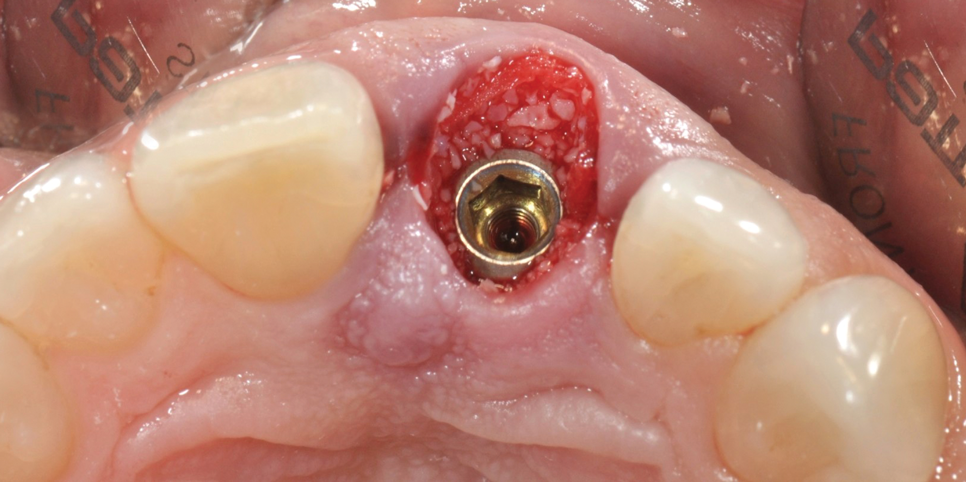

(7.) Restoratively centered guided osteotomy and implant insertion.

Figure 7

(8.) Restoratively centered guided osteotomy and implant insertion.

Figure 8